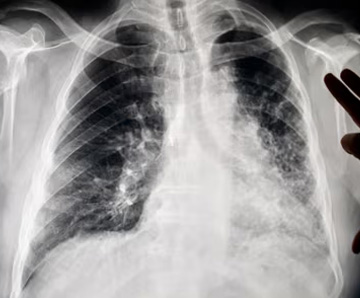

- Silicosis: A lung disease caused by inhaling silica dust.

- Lung Cancer: Long-term exposure increases cancer risk.

- Chronic Obstructive Pulmonary Disease (COPD): Includes chronic bronchitis and emphysema.

Crystalline silica is found in many construction materials, including concrete, brick, mortar, and stone. When these materials are cut, ground, or drilled, fine silica dust can be released and inhaled—causing long-term respiratory damage if not properly controlled.